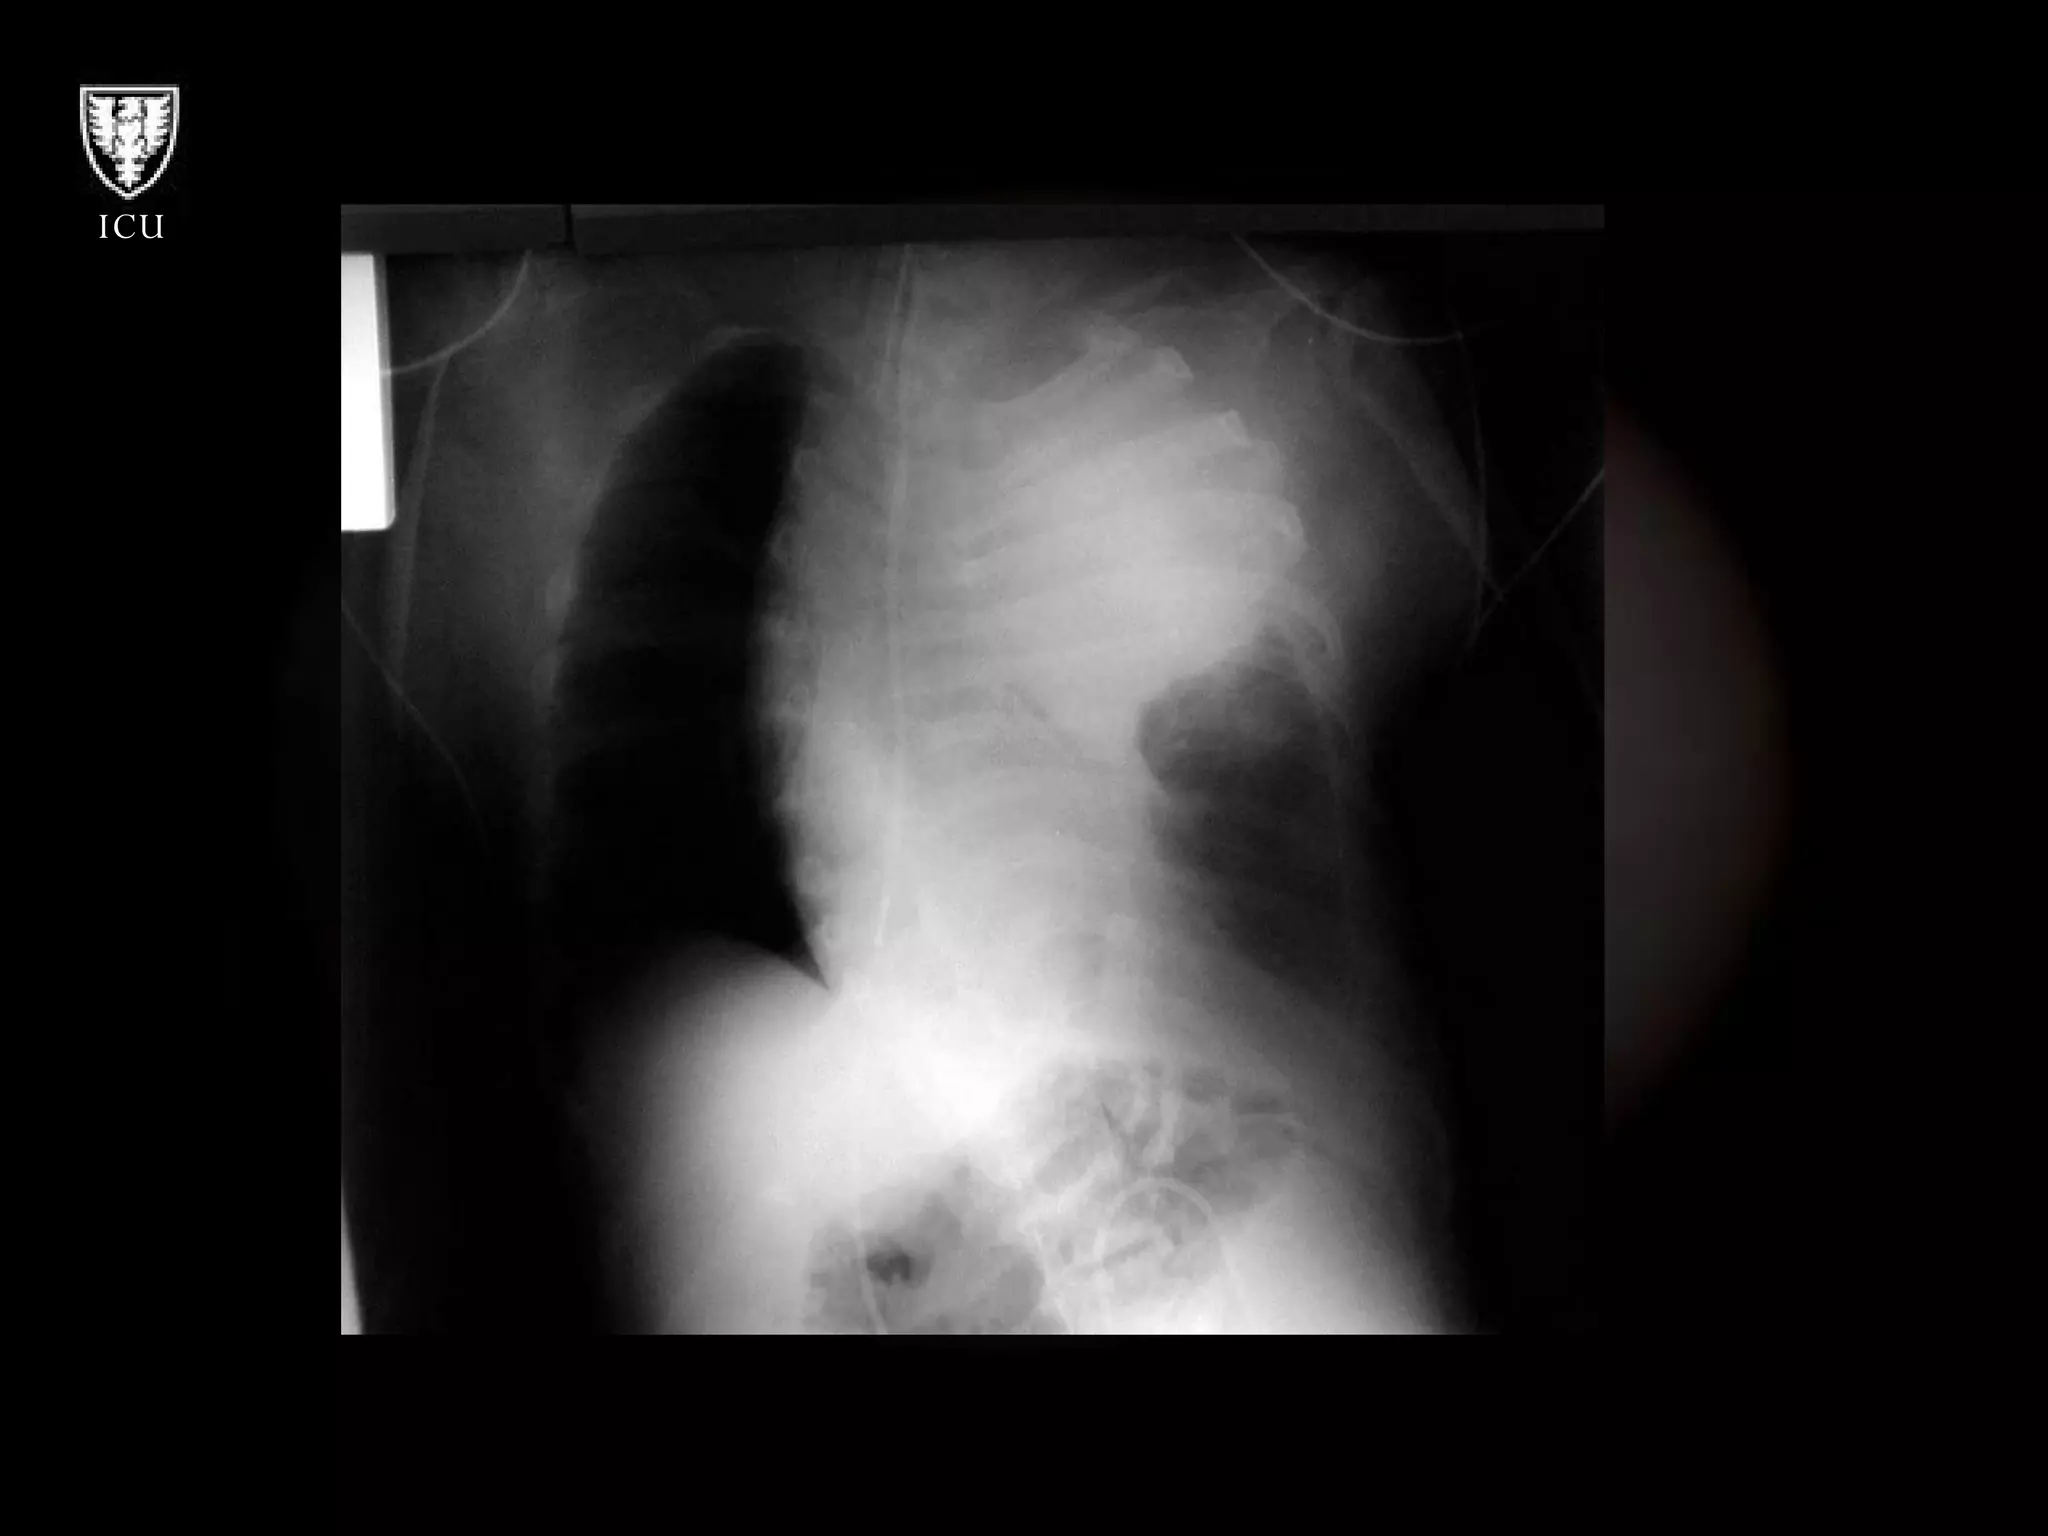

Hematoma After Subclavian Artery Puncture NG ETT

Hematoma After SubclavianArtery Puncture NG ETT